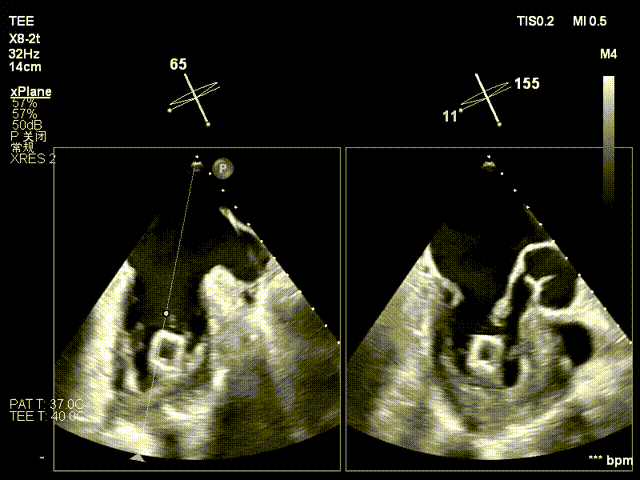

术中操作(关键步骤超声)

在全麻下,于心尖入路完成ValveClamp®装置植入。术中多学科团队密切配合,超声全程实时指导操作。最终,于2偏3区成功植入一枚Ⅲf夹子,一次夹合完成。前叶夹合量12mm,后叶夹合量10mm,反流降至1+,导管操作时间30分钟。术后平均跨瓣压差3mmHg。

术前反流 术后反流